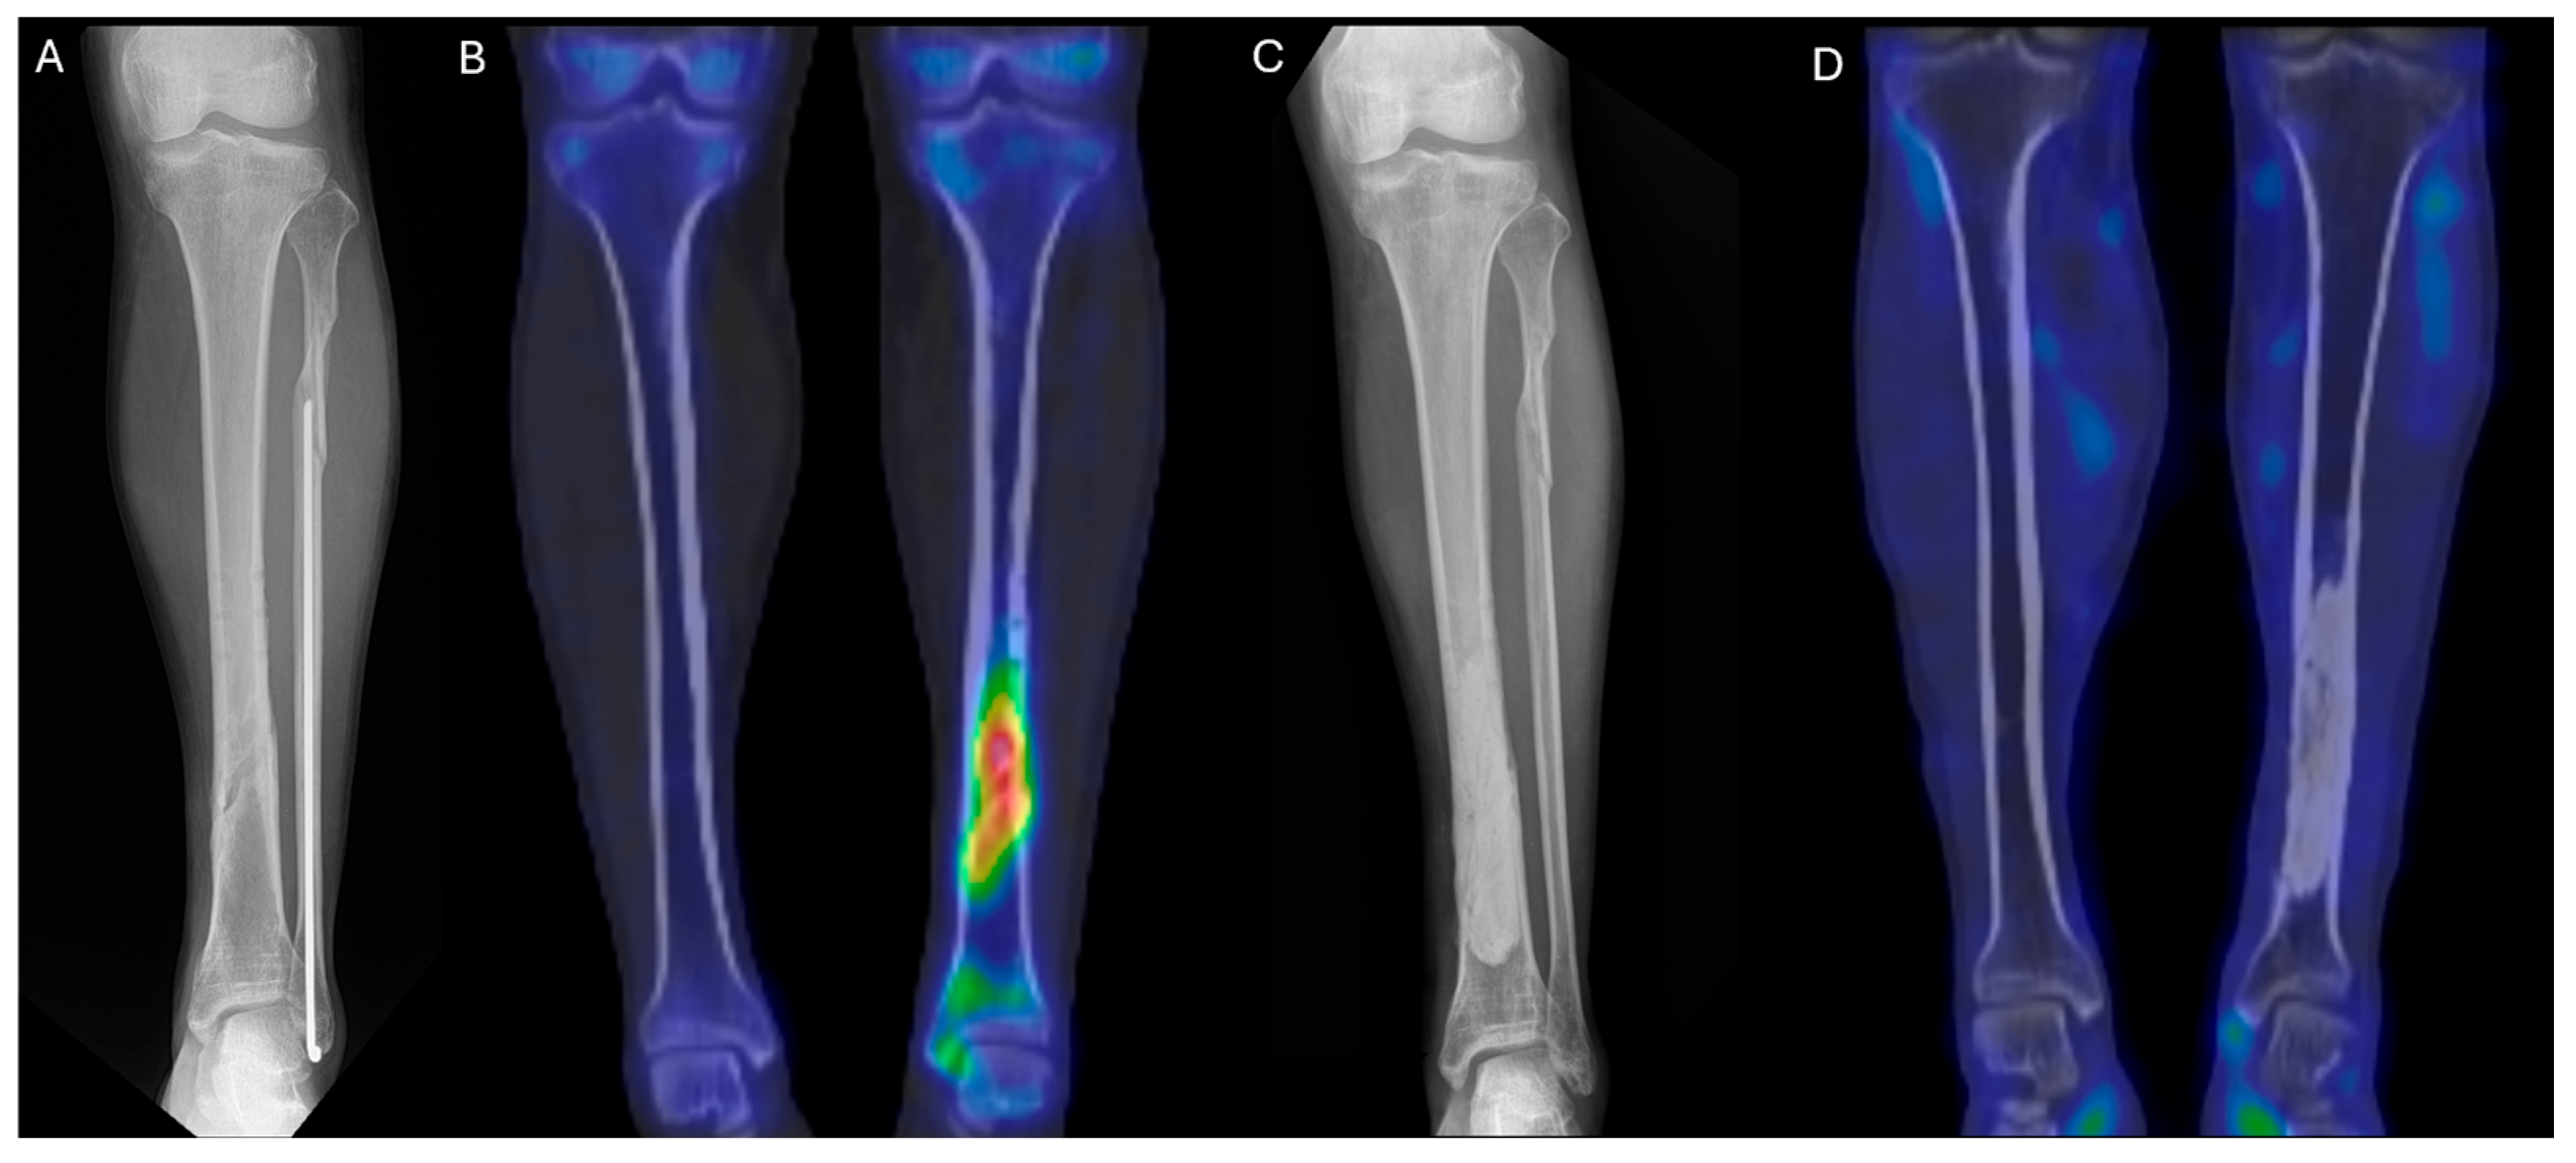

As the infection did not improve, the patient visited our outpatient clinic. He had been receiving intravenous and oral ciprofloxacin for 10 months since the 8-month postoperative day. After the initial visit to our clinic, 99mTc DPD bone SPECT/CT scan was performed, revealing areas of increased uptake, as shown in the images below (Figure 5 and Figure 6).

The patient then underwent surgery, during which extensive debridement was performed on the suspected infected intramedullary lesion. Tissue culture was also taken from the site with the highest uptake on the SPECT/CT scan. Some intramedullary bone marrow was also removed. Antibiotic-impregnated bone cement was inserted into the debrided area.

After surgery, the patient received intravenous antibiotics for two weeks during hospitalization and continued with oral antibiotics for three weeks as an outpatient. At one month postoperatively, plain radiographs showed no specific findings, and at six months, a follow-up 99mTc DPD bone SPECT/CT scan confirmed the absence of high-uptake lesions, indicating that the infection had been successfully controlled. The patient remained free of recurrence and infection for two years.

Figure 5. (A) Preoperative lower leg AP X-ray. (B) Preoperative 99mTc DPD bone SPECT/CT coronal image. (C) Postoperative lower leg AP X-ray at 1 month. (D) Postoperative 99mTc DPD bone SPECT/CT coronal image at 6 months, showing no hypermetabolic uptake, consistent with infection control.